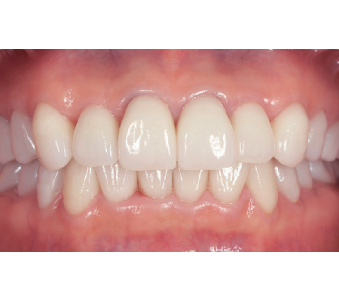

결과로 증명합니다.

국제모아치과의

실제 임상 증례